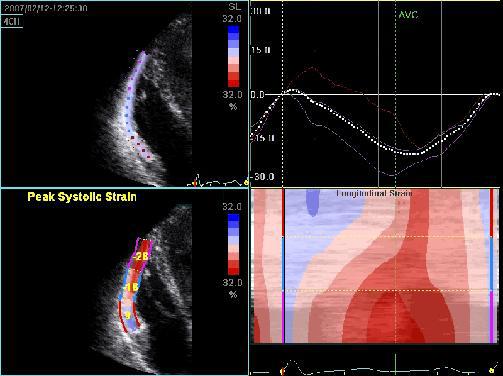

Hypertrophic cardiomyopathy

- 65% Asymmetric hypertrophy of the myocardium, usually the ventricular septum sometimes apical involvement.

- Preserved systolic LV function (EF normal or slightly decreased).

- Predominant impaired diastolic LV function.